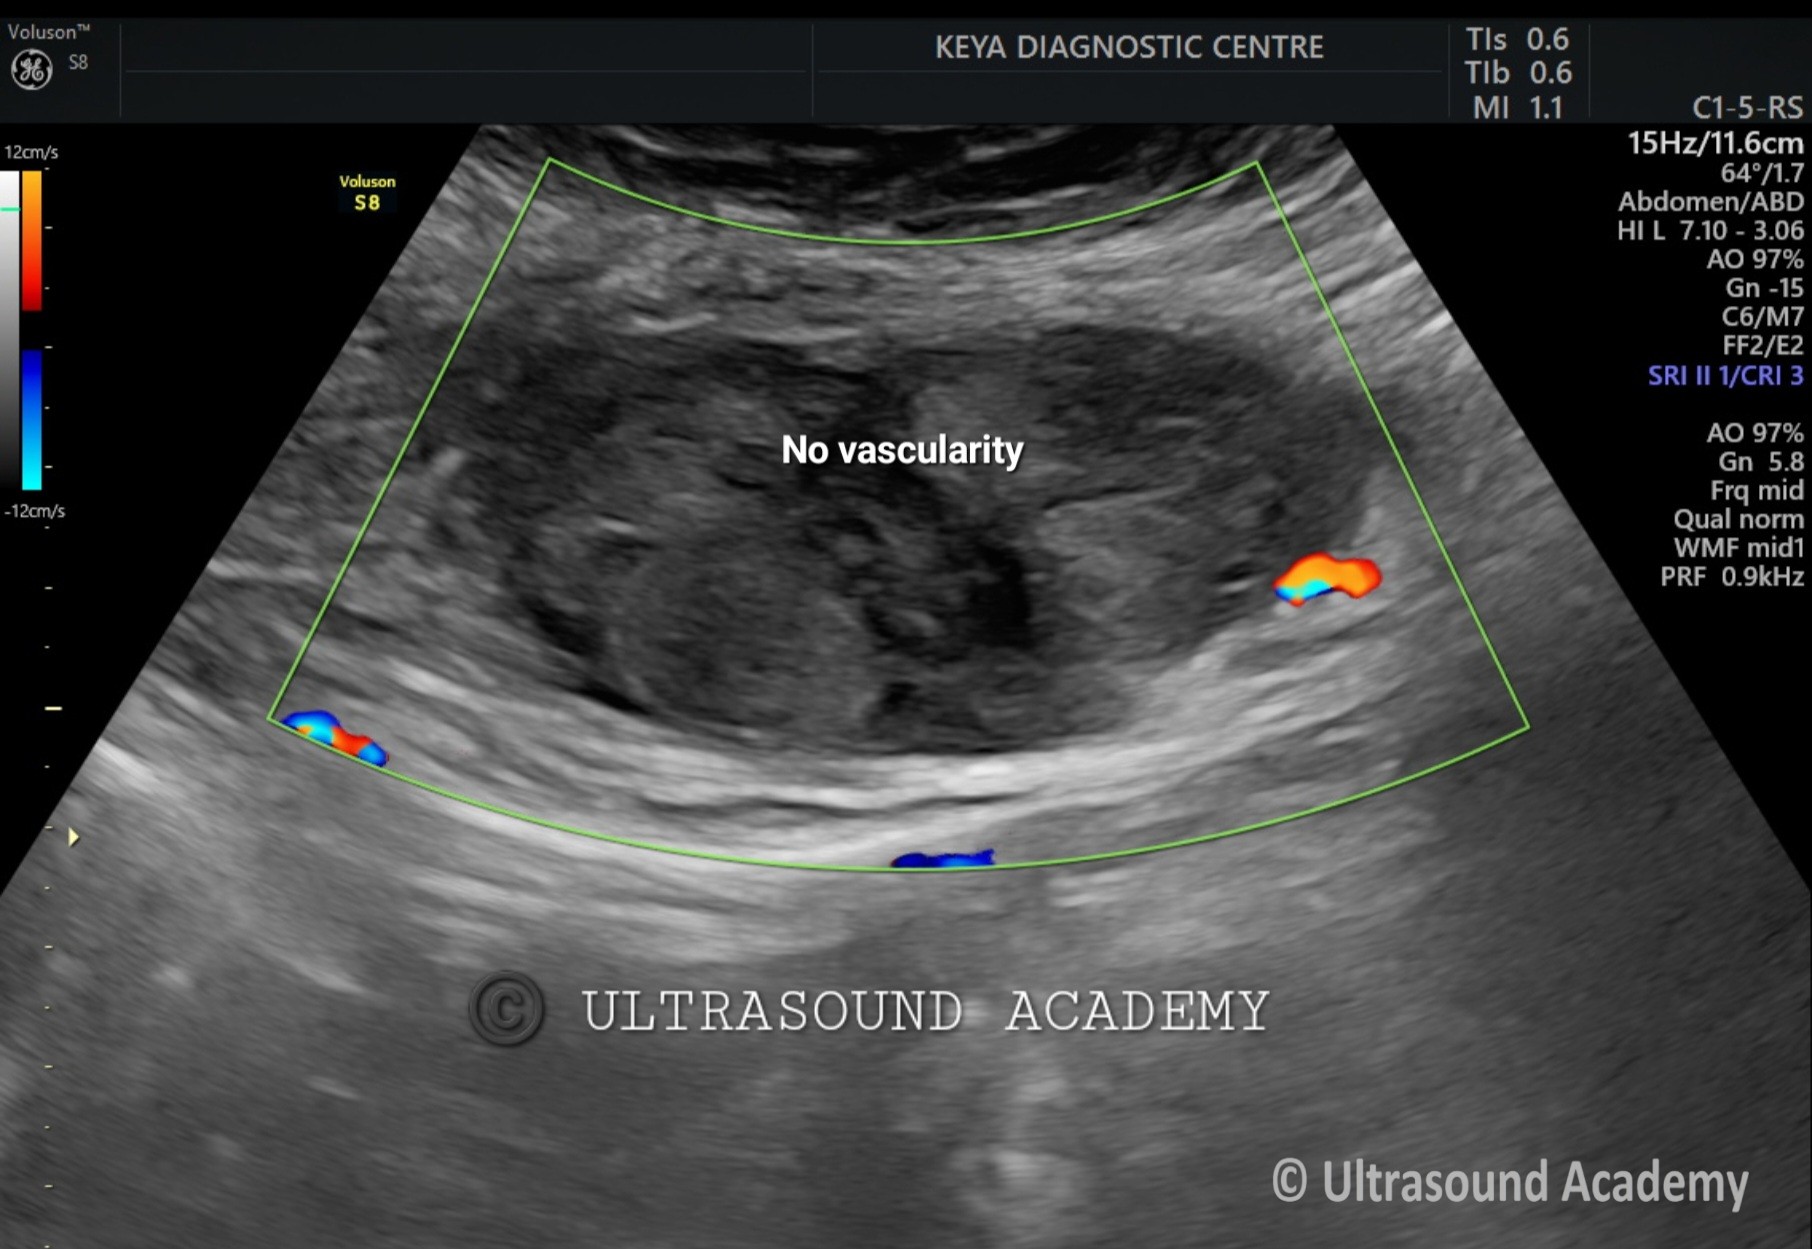

On B mode ultrasound:

There is well defined heterogenous predominantly hyperechoic lesion/ area is seen involving the left rectus abdominis muscle. No intra- abdominal extension is noted.

On Color Doppler examination: No vascularity noted.

So, the diagnosis of acute rectus abdominis muscle hematoma is given.

Doppler Ultrasound Features:

• No significant internal vascularity (distinguishes hematoma from tumors).